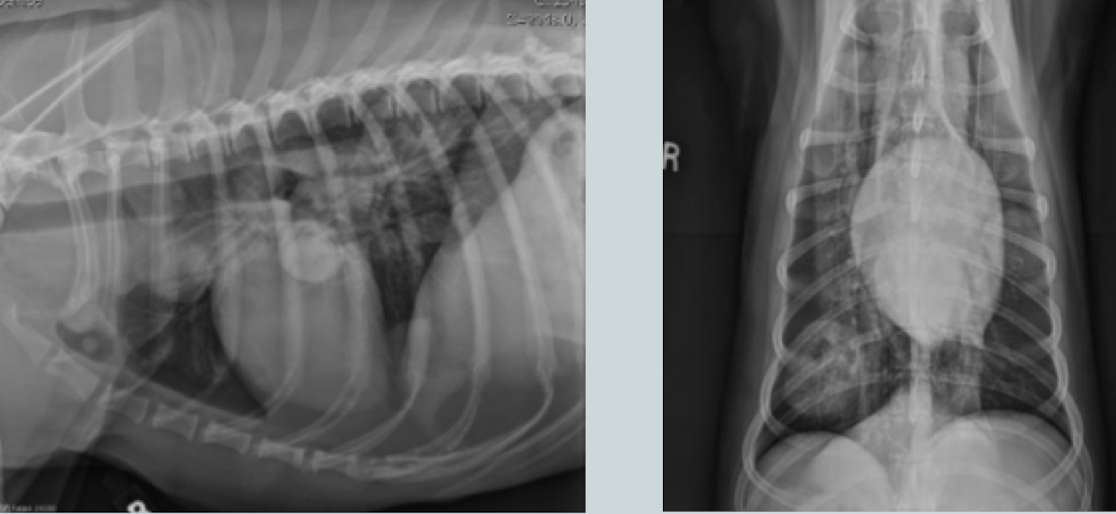

What heart condition?

4 ddx?

globoid cardiomegaly

pericardial effusion

dilated cardiomyopathy

peritoneal pericardial diaphragmatic hernia

severe tricuspid valve disease